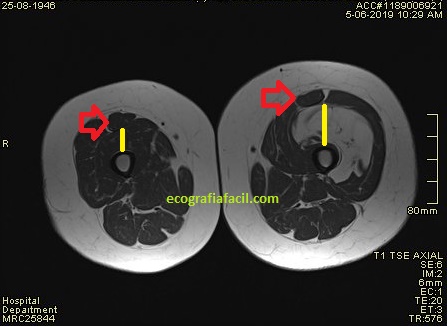

En la primera imagen encuentro ya los cambios referidos en el párrafo anterior. Inmediatamente en la imagen 2, comparativa de ambas estructuras, patológica y normal.La imagen 3 es una imagen correlacionada de RM, potenciada en T1 para que veas el mismo corte con dos técnicas diferentes, ambas en corte axial.

Los hallazgos demostraron en la porción distal del músculo afectado y en ambas técnicas, una zona sensiblemente diferente, de aspecto anómalo, que con la inyección de contraste endovenoso se comprobó ligera captación patológica. Parece una afectación global del Músculo Crural por infiltración grasa (gran lipoma) donde hay cambios en una región de este, la distal, en relación con cambios por Metaplasia o algún tipo de patología infiltrante a estudiar con anatomía patológica.